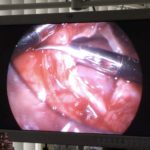

9歳の柴犬が散歩中に突然倒れる事があるとのことでかかりつけを受診しました。幼少時よりてんかん発作を発症する事があるが、今回の様子はてんかんの時とは異なる様だとのことで精査を希望され来院しました。心音は微弱でマッフルを呈していました。また、腹水の貯留も確認されました。心臓超音波検査では心膜液の貯留が確認されました。心嚢水の除去を行なったところ、出血性の心嚢水でした。数日間は心嚢水の除去のみで一般状態は改善していました。しかし、再発すると虚脱するといった症状が確認されたため、再発性の心タンポナーゼを回避するために、胸腔鏡下で心膜切除術を実施しました。同時に中皮腫、血管肉腫、特発性との鑑別にCTによる精査も実施しております。心膜の病理検査では腫瘍性の変化はなく、著しく繊維化した心膜であり、特発性と診断されました。胸腔鏡下での手術であったため、数日間の入院で痛みも少なく良好に経過しています。